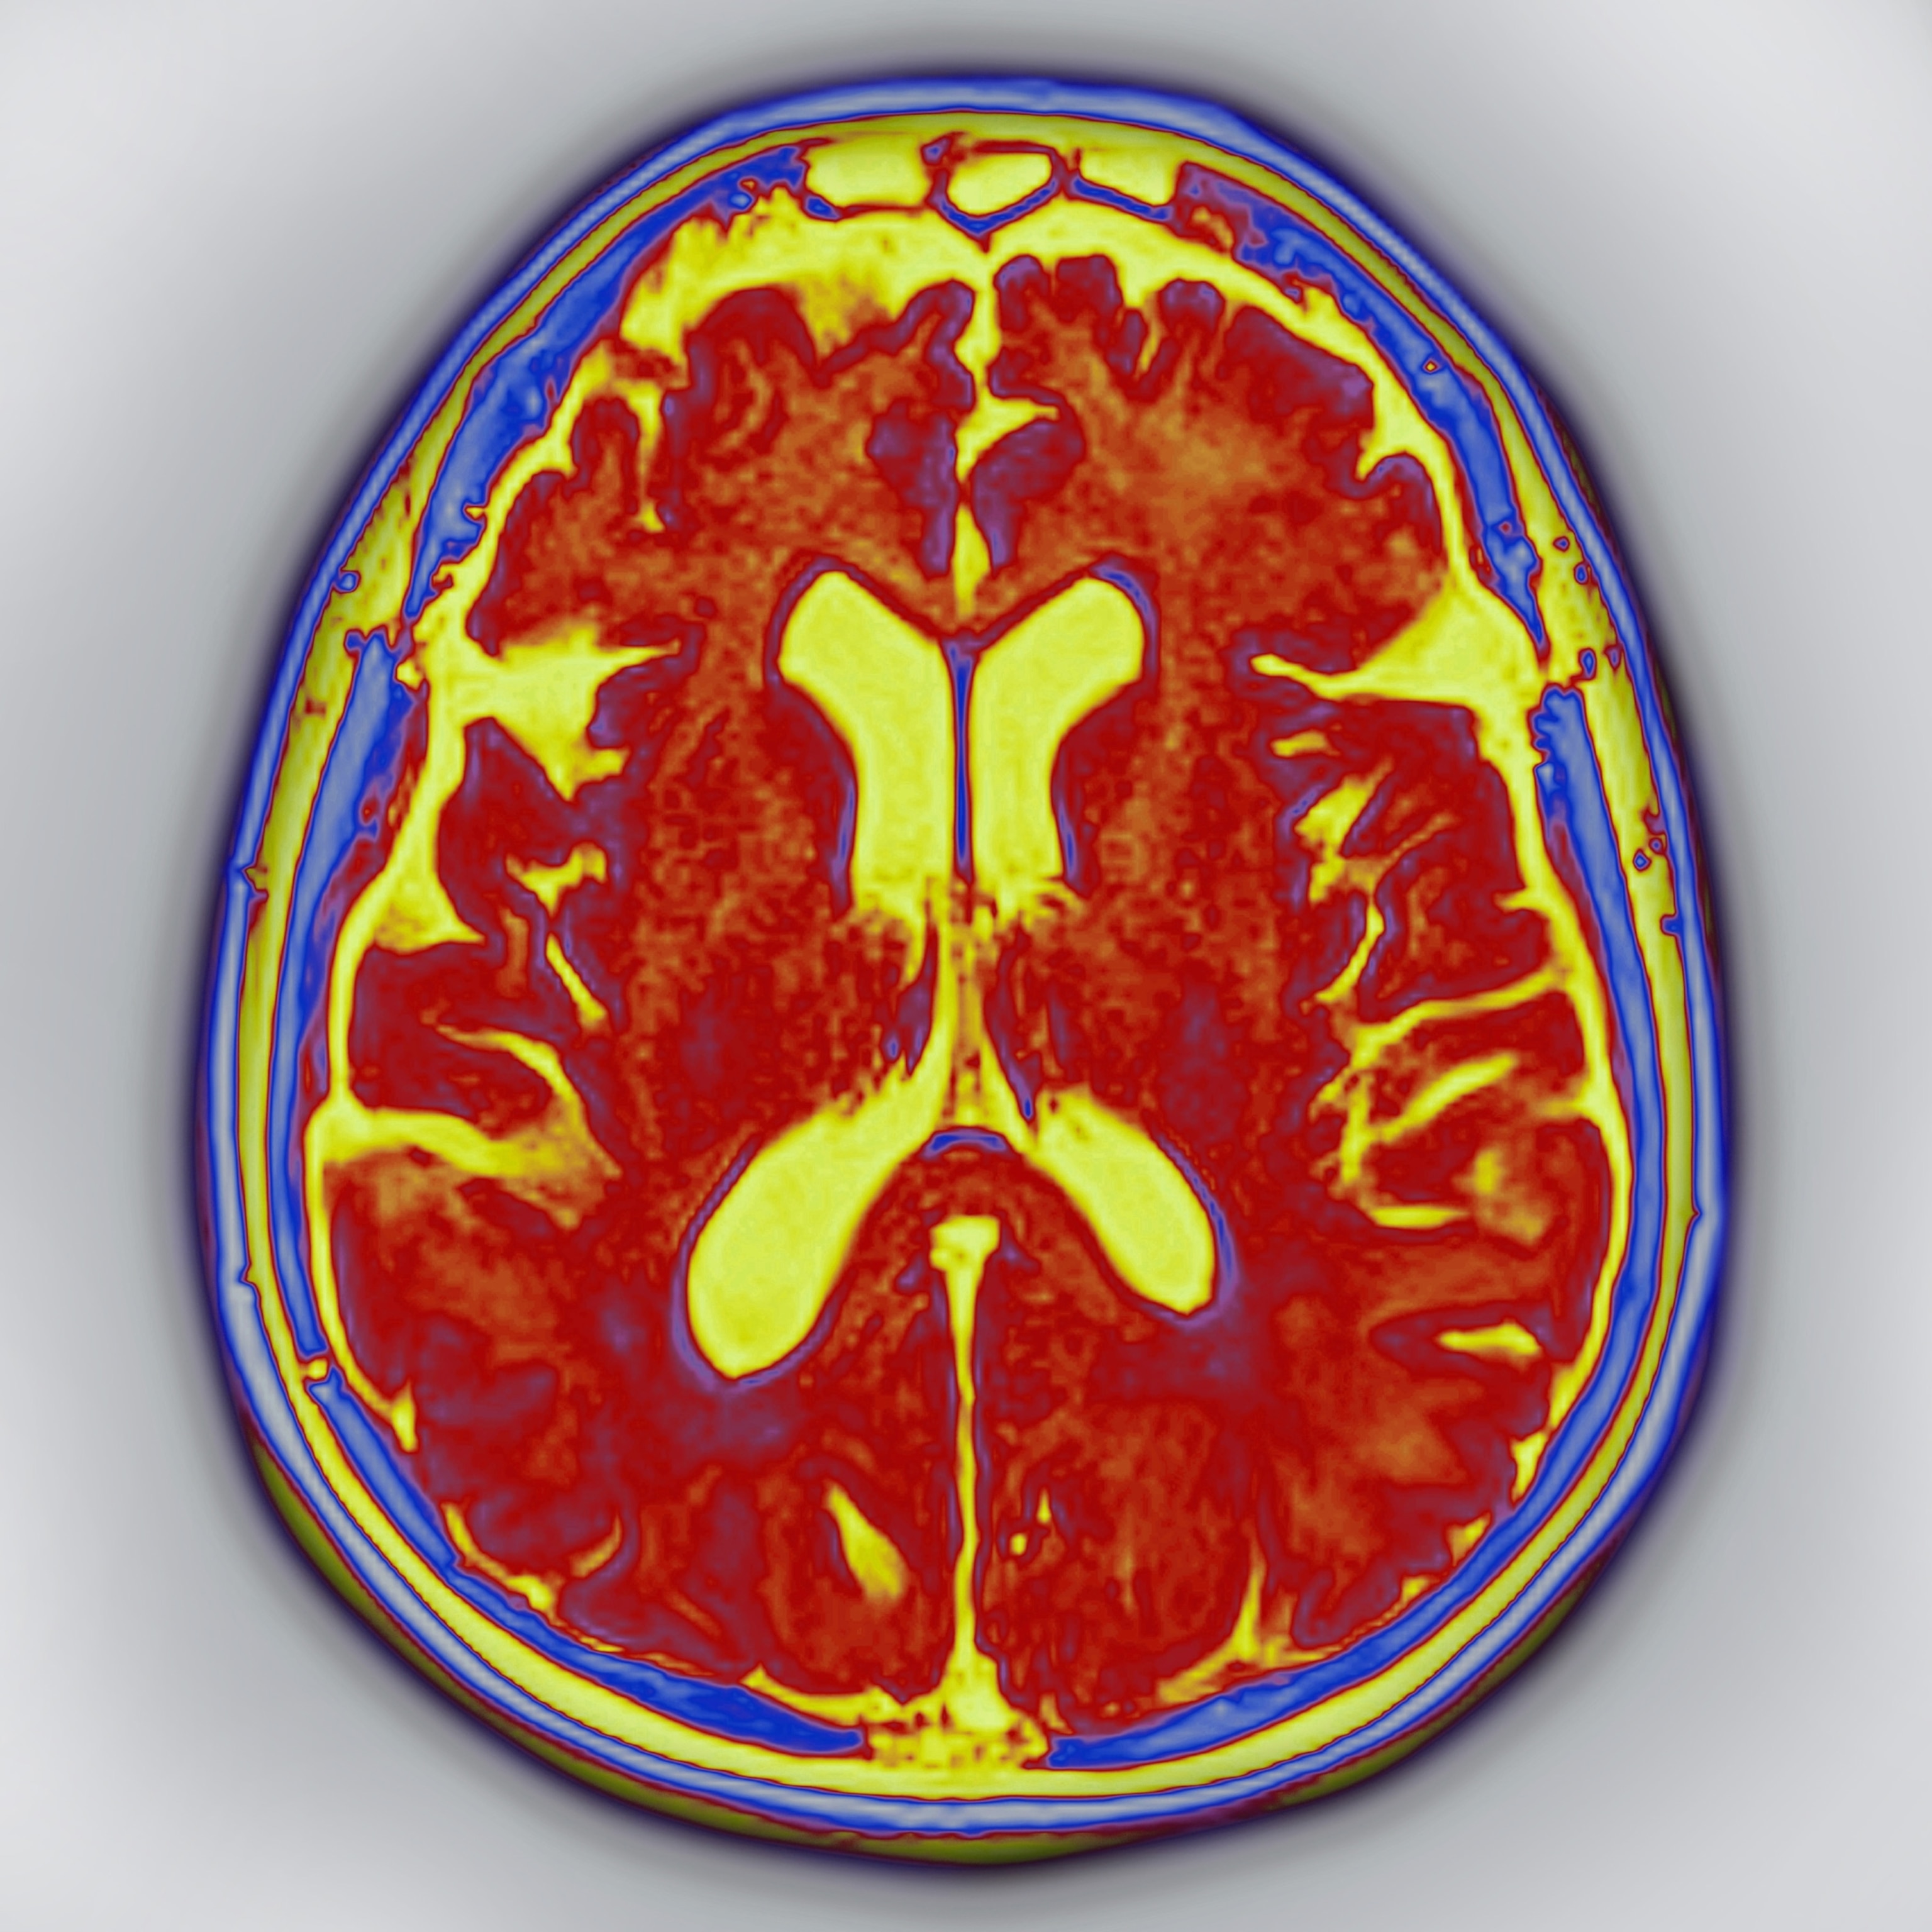

The brain’s plasticity reveals much about its amazing structure. It is the most complicated object we’ve yet discovered in the universe, composed of billions of independent units that work together in remarkably complex symphonies that manage to comprehend the world; process, store, and retrieve information; and use that information to decide how to interact with the world. Each new experience changes the brain’s physical makeup, so that by the time you finish reading this page, your brain will be slightly different from your brain at the time you began with the page’s first word.